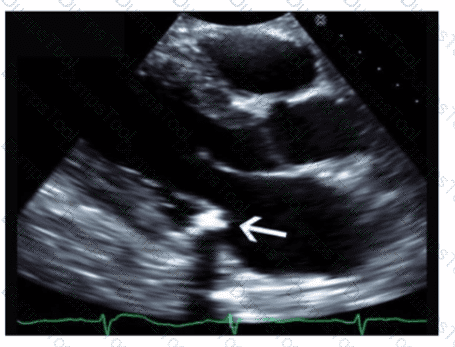

An intravenous drug user presents with a fever of unknown origin, flu-like symptoms, dyspnea, and chest pain. Which ultrasound finding is mostly likely associated with this presentation?